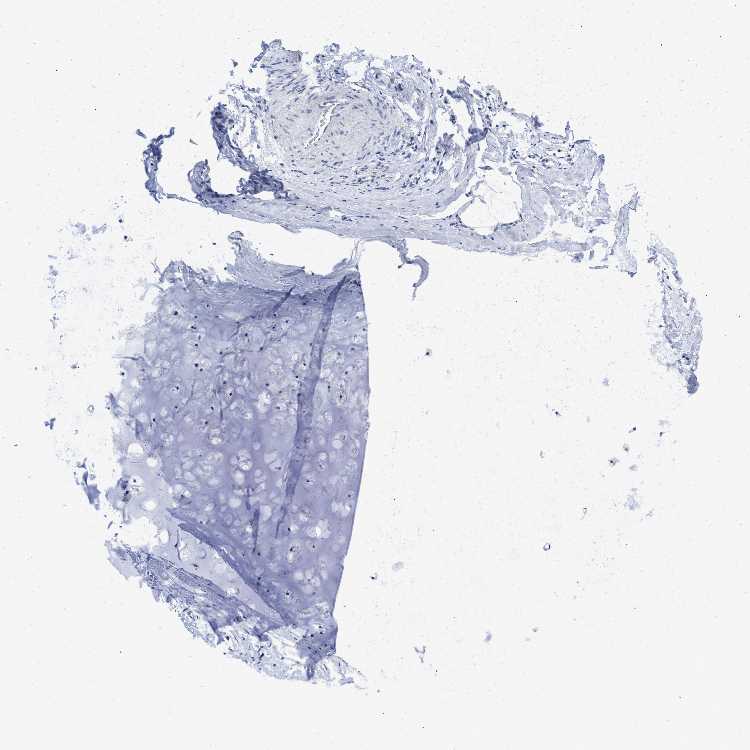

ADIPOSE TISSUE - Antibody stainingi

Antibody staining in the annotated cell types in the current human tissue is reported as not detected, low, medium, or high, based on conventional immunohistochemistry profiling in selected tissues. This score is based on the combination of the staining intensity and fraction of stained cells.

Each image is clickable and will lead to virtual microscopy that enables deeper exploration of all samples and also displays staining intensity scores, fraction scores and subcellular localization as well as patient and tissue information for each sample.

Antibody HPA010973Antibody CAB016734

Adipocytes Not detectedNot detected